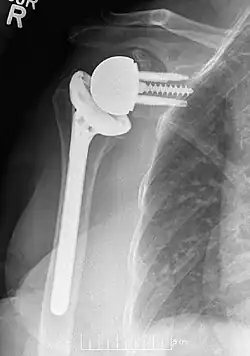

![]() Radiografía simple en vista anteroposterior (AP) del estado de un hombro derecho tras una artroplastia inversa de hombro utilizando una prótesis con centro de rotación lateralizado. | ||